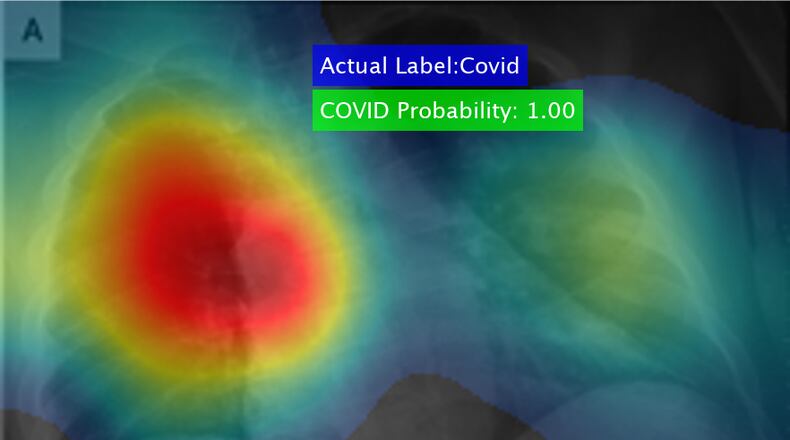

The software, developed by UDRI research scientist Barath Narayanan, uses a “deep learning” algorithm that searches for markings on X-rays that indicate the presence of COVID-19, the university said.

Using medical imaging including X-rays, CT scans, blood smear slides and eye scans, Narayanan had already developed a number of software codes that successfully detect—with 92 to 99 percent accuracy—lung and breast cancers and other conditions.